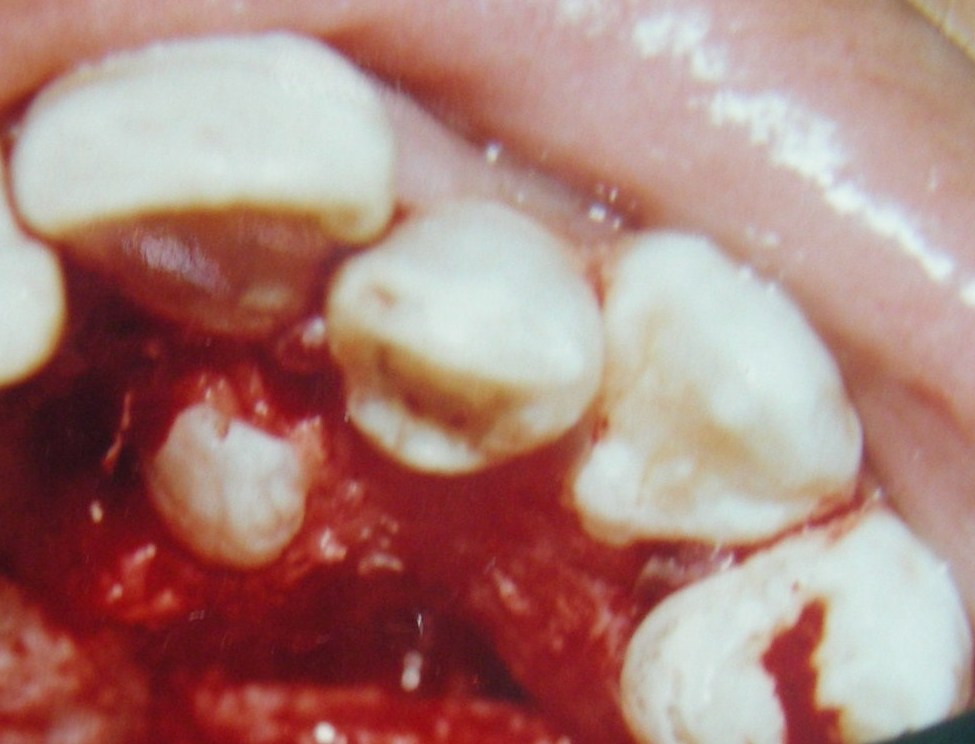

Dentigerous cyst is a developmental odontogenic cyst associated with unerupted teeth, odontomes or supernumerary teeth. About 95% of dentigerous cysts involve the permanent dentition and only 5% are associated with supernumerary teeth. Supernumerary teeth should be examined very carefully to prevent possible effects on adjacent regular teeth and possible cystic development . Dentigerous cysts are usually slow-growing lesions and may attain a considerable size with minimal or no symptoms. Ameloblastoma, mucoepidermoid carcinoma, and squamous cell carcinoma have also been reported to arise from the lining epithelium of dentigerous cysts, indicating the pluripotentiality of their cells. Early detection and removal of such cysts is therefore important to reduce potential morbidity. A rare case of a twelve year old boy with two supernumerary teeth, of which one was associated with dentigerous cyst is described here along with the treatment strategy employed for the patient.